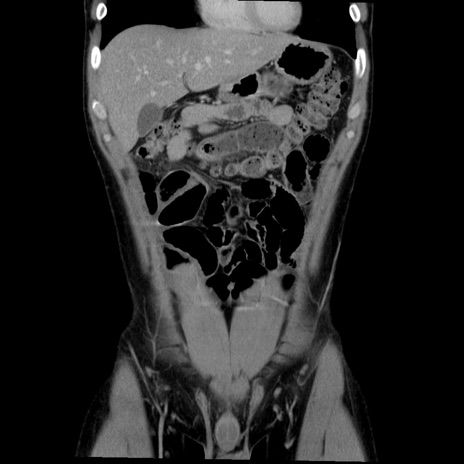

症例36(冠状断像)

【症例】20歳代 男性

【主訴】心窩部痛

【現病歴】今朝より上腹部痛あり。一旦軽快していたが再度出現したため救急要請。昨日夕に白身の魚を含む刺身を食べた。

【身体所見】BP 136/89mmHg、HR 74/min、BT 37.0℃、腹部:膨満、軟、心窩部に圧痛あり。反跳痛なし、筋性防御なし、腸雑音やや亢進あり。

【データ】WBC 17700、CRP 0.48